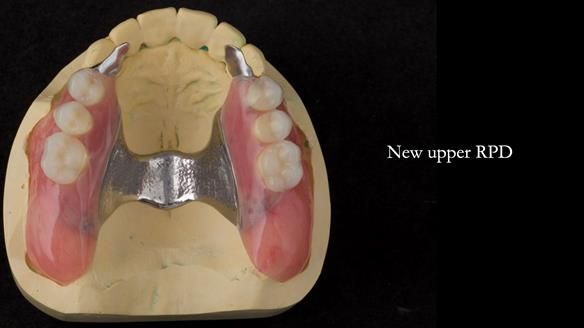

Replacement lower overdenture & upper RPD for Jackie

This Newsletter show Jackie’s case from start to finish – a technically demanding case involving replacing a telescopic crown-supported lower overdenture and an upper precision attachment-retained partial denture.

It turned out to be a success – Jackie was super happy.

However, it was far from straightforward.